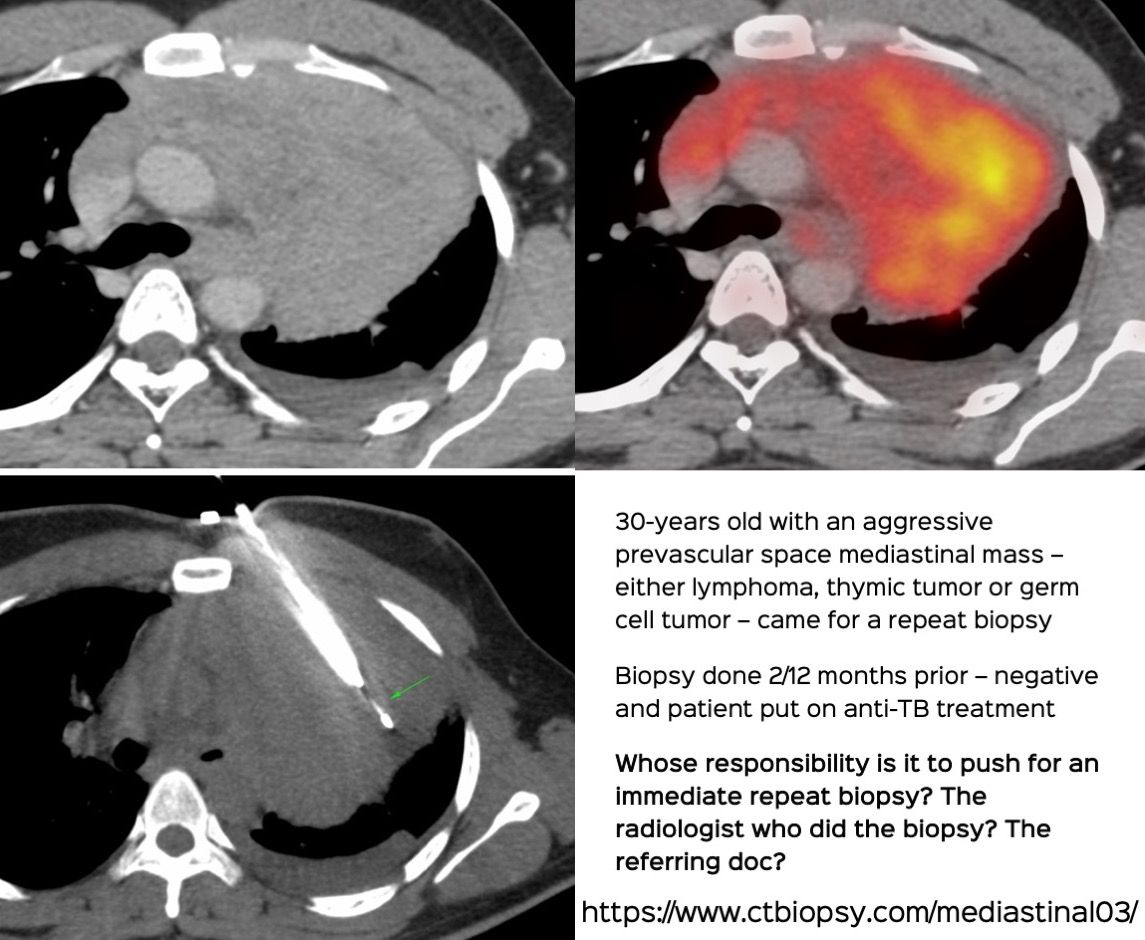

Case 69: Whose Responsibility is It After a Negative Biopsy to Push for a Repeat Biopsy?